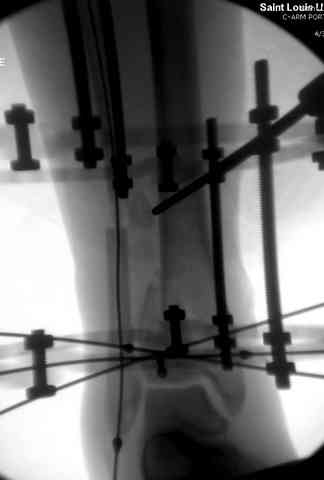

Снова приветствую вас, коллеги. К моменту вступления в обсуждение аксакалов, операция была, увы, выполнена(31.10.07.) Начали с доступа к наружной лодыжке, произвели ее фиксацию спицами, развернули кусок заднего края, наложили дистрактор, затем произвели дистракцию, фиксацию спицами дистального эпиметафиза б/бк,Рентгено-контроль. синтез наружной лодыжки 1/3пластиной. из двух коротких разрезов сформирован канал под медиальную тибиальную пластину LCP. Края ран ушиты без натяжения. Прочувствовать жесткость фиксации винтами с угловой стабильностью не удалось, поэтому дистрактор оставлен на энное время.

На представленных R-снимках не окончательный вид после остеосинтеза. Дистальная опора давила на стопу, пришлось ее сместить проксимально, в рез-те чего, она закрыла щель сустава, последние снимки не информативны.